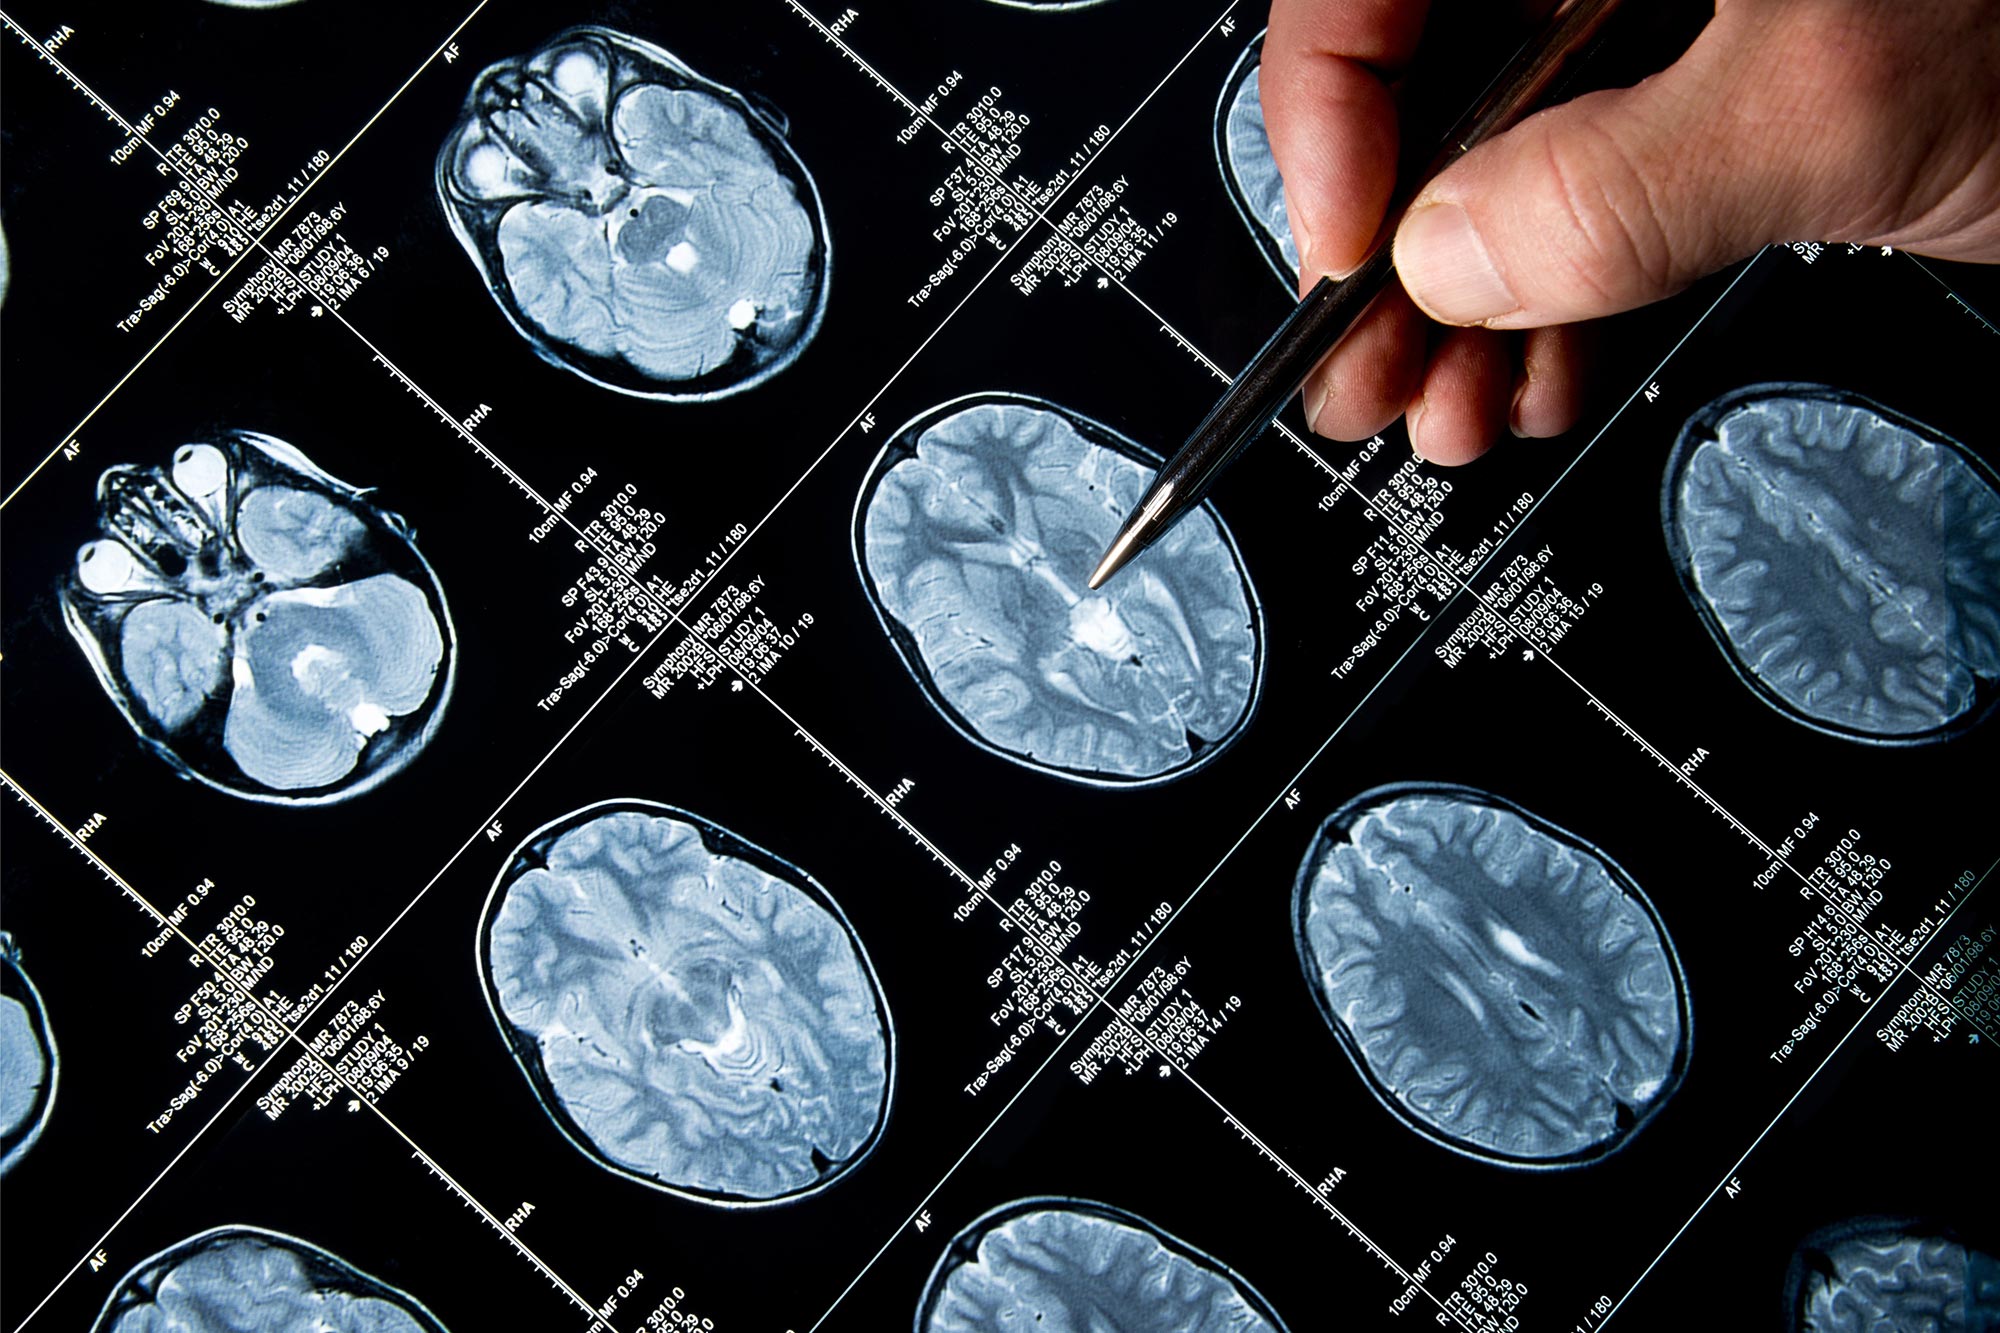

Untuk menyiasati hal ini, Dr. Brown dan rekannya menggunakan algoritma yang dikembangkan menggunakan pembelajaran mesin untuk menganalisis pemindaian otak MRI yang diambil dari 1.351 orang dewasa muda di berbagai skor BMI, mencari perbedaan di hipotalamus ketika membandingkan individu yang memiliki berat badan kurang, berat badan sehat, kelebihan berat badan, dan hidup dengan obesitas.

Dalam sebuah penelitian yang diterbitkan di Neurogambar: Klinistim menemukan bahwa keseluruhan volume hipotalamus secara signifikan lebih besar pada kelompok dewasa muda yang kelebihan berat badan dan obesitas. Faktanya, tim menemukan hubungan yang signifikan antara volume hipotalamus dan indeks massa tubuh (BMI).

Perbedaan volume ini paling jelas terlihat pada sub-wilayah hipotalamus yang mengontrol nafsu makan melalui pelepasan hormon untuk menyeimbangkan rasa lapar dan kenyang.